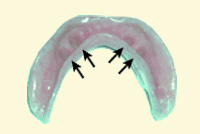

An overdenture in a patient's mouth